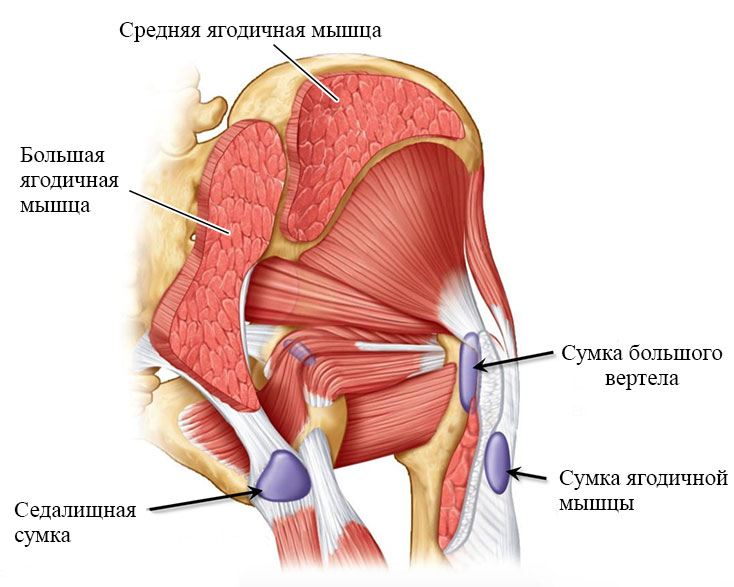

Здоровье суставов: Трохантерит и его влияние на мышцы